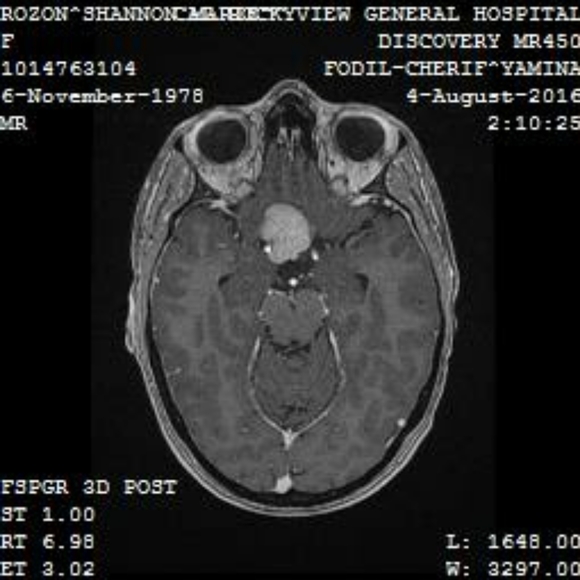

I have been diagnosed with recurrent Optic Chiasm II Meningiomas. The second battle in 4 years. The first tumor in my brain was removed by emergency surgery through the front of my face.

This 2nd one is hit with direct brain radiation so hopefully it doesn't cause the trauma the 1st one did. This does come with side effects and risks. I'm on week 2 of 6.